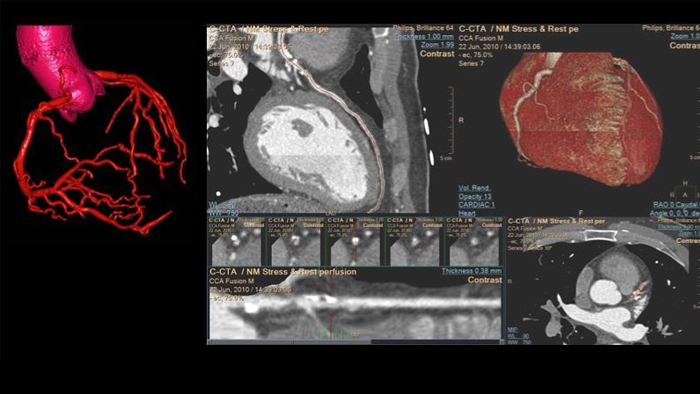

Unlock the full potential of CT as a non-invasive cardiac diagnostic tool.